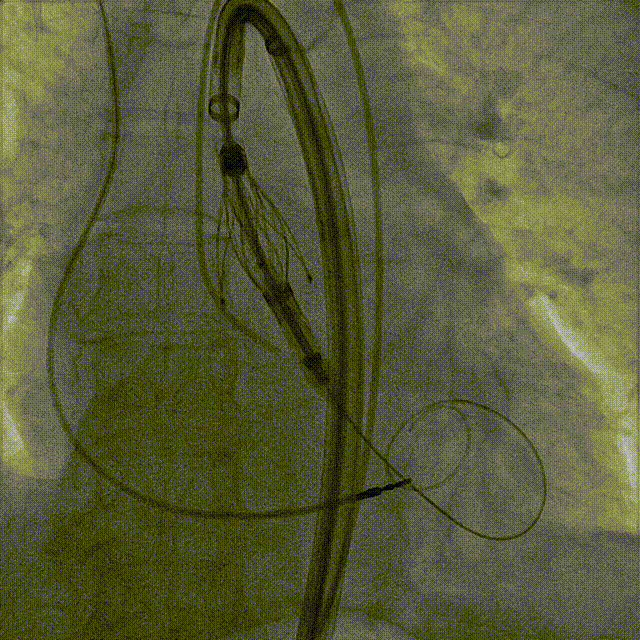

手术过程:5A 标准化流程SOP

右窦中心造影

大鞘到STJ

瓣膜调弯后解离

瓣膜右窦中心调整

定位键窦不对齐

灵活旋转操作

确认窦对齐

入窦

无窦超选验证

左窦超选验证

一键释放

术后造影